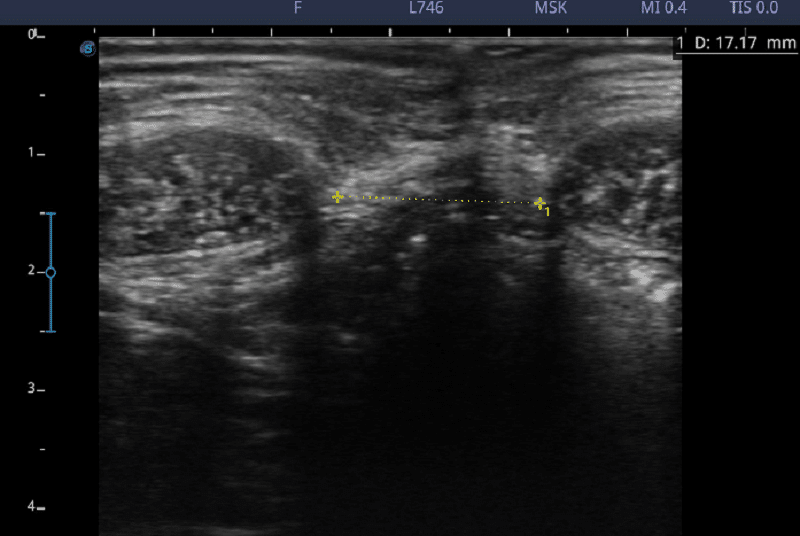

エコー写真は、M様の治療前後の効果を示しています。

【治療前 21.75㎜】

【治療後 17.17㎜(-4.58㎜ 離開 減少)】

治療後すぐから腹直筋離開が改善していることが明らかになった。

治療後も効果が残ることが分かった♪

治療を継続することで、腹直筋離開が改善することが判明した!!